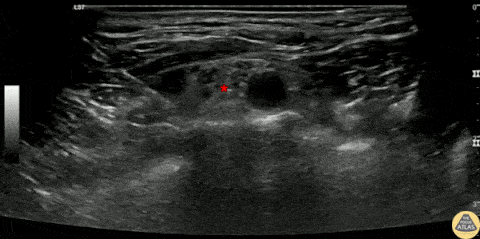

60s F presented with arm pain after a fall out of a wheelchair, and was found to have a proximal humerus fracture. A supraclavicular brachial plexus block was placed for analgesia. The brachial plexus is seen here, lateral to the pulsating subclavian artery, superficial to the first rib. The block is shown with the needle entering from the lateral aspect, depositing anesthetic adjacent to the brachial plexus just superficial to the first rib, which acts as a physical backstop, helping reduce the risk of inadvertent pneumothorax. Pleural slide is seen deep to the first rib lateral and medial , highlighting the proximity and underscoring the importance of keeping the entire needle in view during the entire nerve block procedure. This patient had improvement in their pain and was able to be discharged home. Dr. Greg Wiener, PGY4 Denver Health Residency in Emergency Medicine